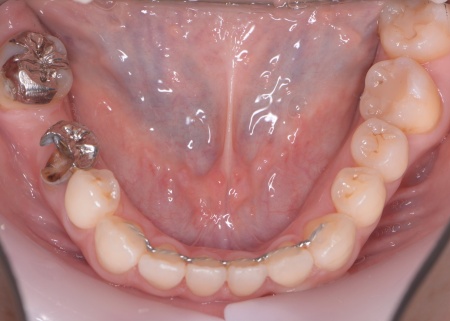

| カウンセリング | 拝見したところ、左下と右上の歯はともに大きな虫歯があり、歯だけでなく被せ物を支える土台の部分にも影響が及んでいました。

さらに、ほかの歯に入っている詰め物や被せ物の周囲にも、過去に治療した部分に再び虫歯ができる二次カリエスが複数見つかりました。 また、噛み合わせを確認したところ、奥歯で噛み合わせた際に上下の前歯が当たらず隙間ができる開咬(かいこう)が認められました。 実際に患者様の場合も、特定の歯に長期間強い力がかかり続けたことで歯や修復物の破損、さらには口腔内全体のトラブルにつながった可能性が高いと考えられました。 修復治療が必要でしたがこの噛み合わせの問題を改善しないまま行うと、治療した歯に再び過度な力が加わって被せ物の破損・脱離や虫歯の再発を招くリスクが高まります。 |

まずは矯正治療を優先し、噛み合わせが整ってから虫歯の再発リスクの低いセラミックの被せ物・詰め物などで歯の形態と機能を回復する方針を提案し、同意いただきました。

矯正治療については、専門的な診断と管理が必要と判断したため専門の矯正歯科医院をご紹介し、他院にて実施していただきました。 矯正治療終了後、改めてお口の中を確認したうえで、歯の状態に合わせ虫歯の除去や土台の修復を丁寧に行い、精密な型取りを実施しています。 最後に噛み合わせ全体のバランスを確認しながら新しく作製した被せ物や詰め物を装着し、見た目に問題がないか、噛み合わせが安定しているかを確認し、治療を終了しました。 |